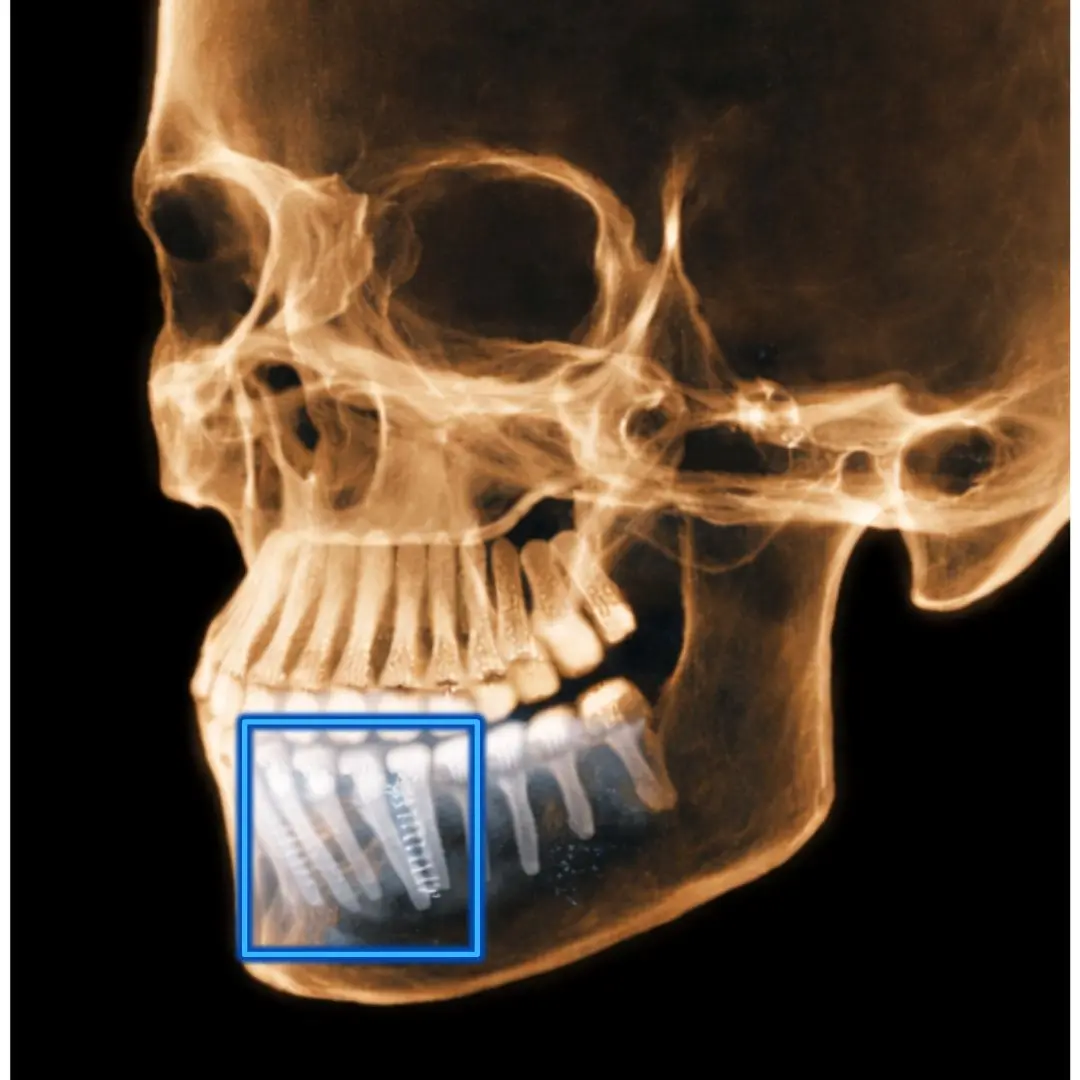

Son estudios 3D avanzados que generan  imágenes tridimensionales muy precisas de los dientes, huesos maxilares, articulación temporomandibular (ATM), senos maxilares y conducto dentario.

TOMOGRAFÍA DE IMPLANTES

Cuando es necesario evaluar las condiciones óseas de los rebordes alveolares.